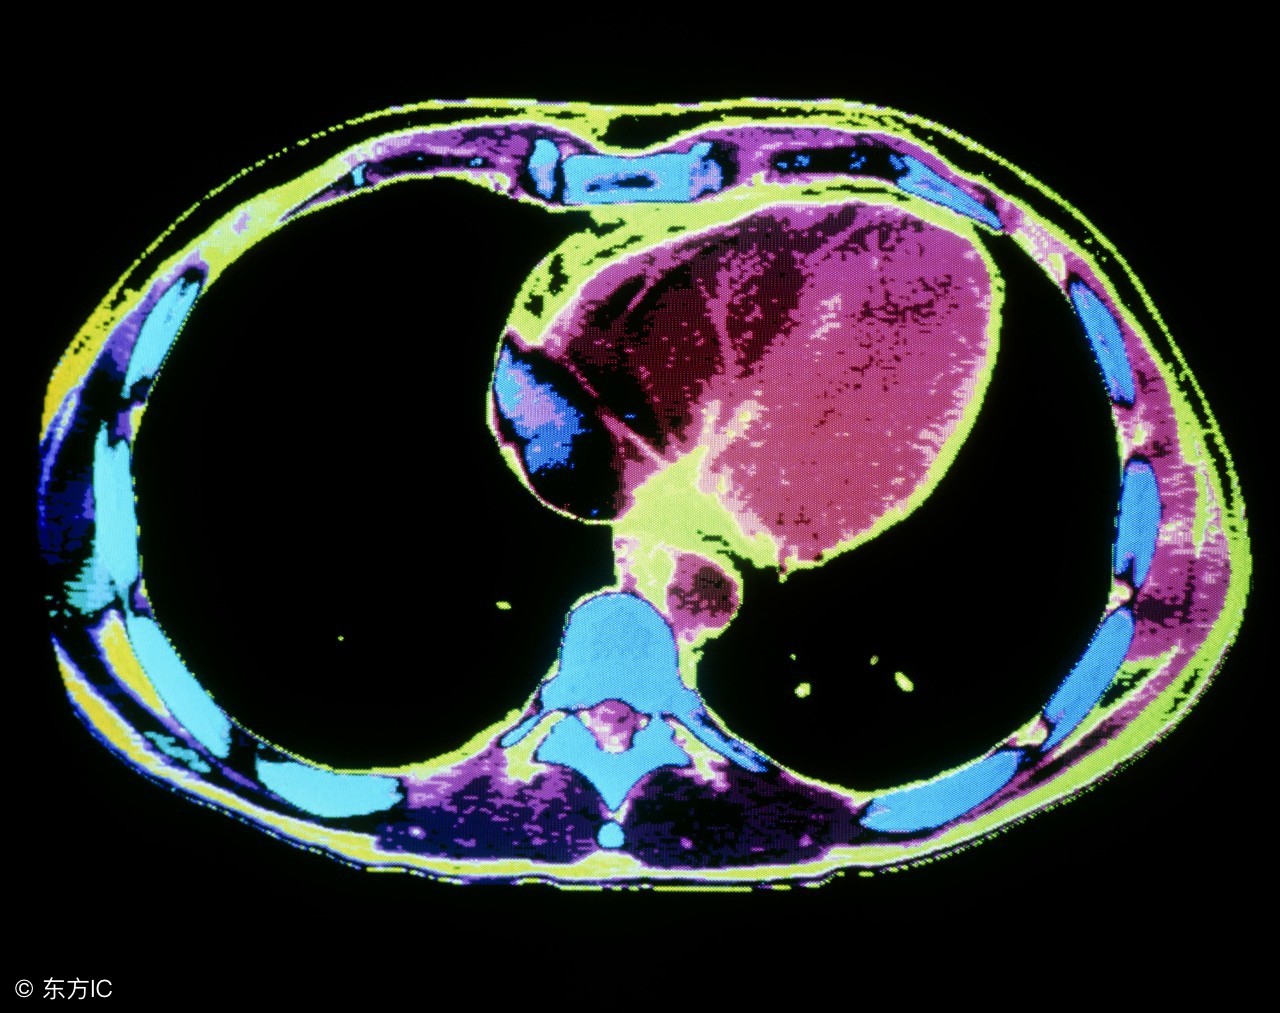

胸部增强CT:了解可以病变处食管壁是否增厚,侵及食管壁的深度,与周围器官主要是气管的关系,是否侵犯,以及纵膈内淋巴结转移的情况。顺便了解双肺情况及胸膜情况。

胸部CT可以了解肿瘤侵犯食管壁的深度及周围淋巴结